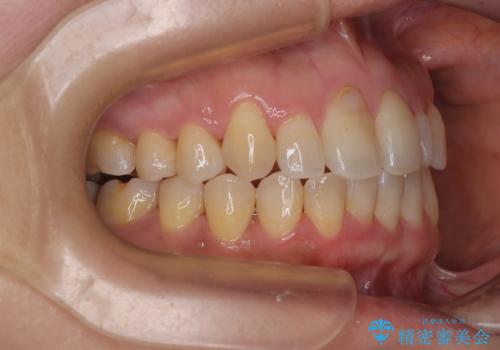

下顎骨が左側にズレて成長してしまったため、左側の咬み合わせが上下反対になっている状態でした。

そこまでの処置は望んでいらっしゃらなかったため、歯列矯正でのカムフラージュにより咬み合わせを改善することとしました。

予想通り左側の咬み合わせの調整に苦労をしましたが、最終的には違和感のない咬み合わせを達成することができました。